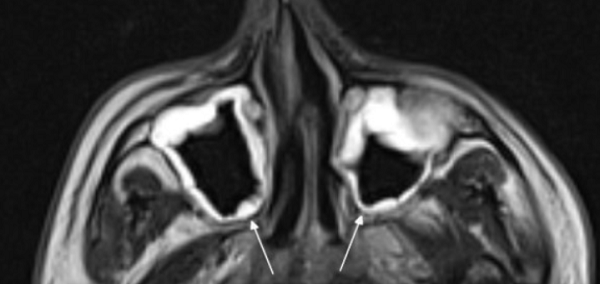

На снимке концентрическая воспалительная гипертрофия (указана стрелками) слизистой оболочки гайморовых пазух

Концентрическая воспалительная гипертрофия ячеек решетчатой кости (указана стрелками)